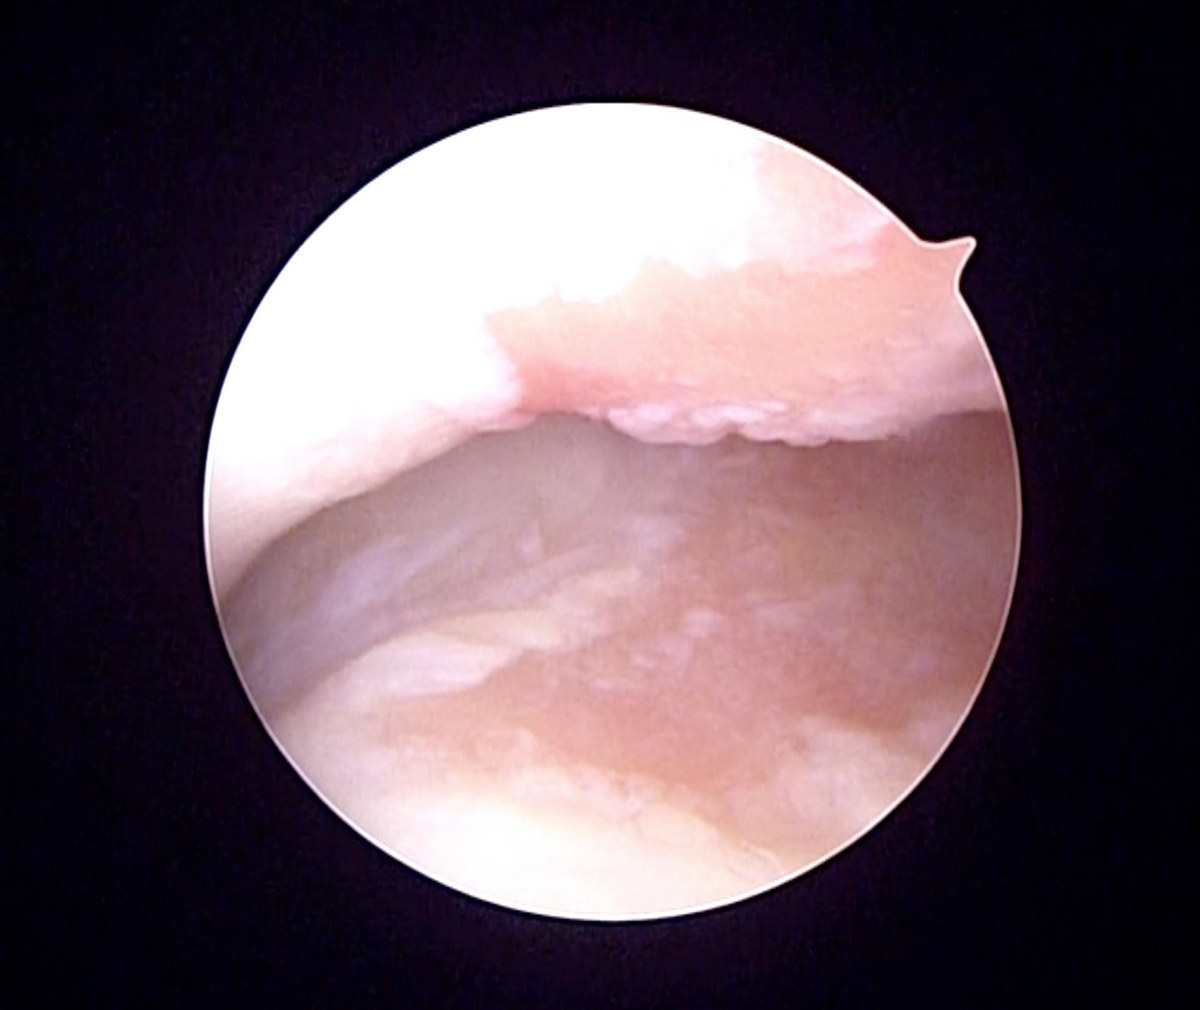

確定診断のため、関節鏡検査を実施したところ、下の写真のように、肘関節の内側の関節軟骨(正常は白色)が消失し、軟骨の下の骨が露出(ピンク色の部分)している状態でした。

診断名は、『左肘関節内側軟骨損傷(Medial Compartment Disease)』でした。